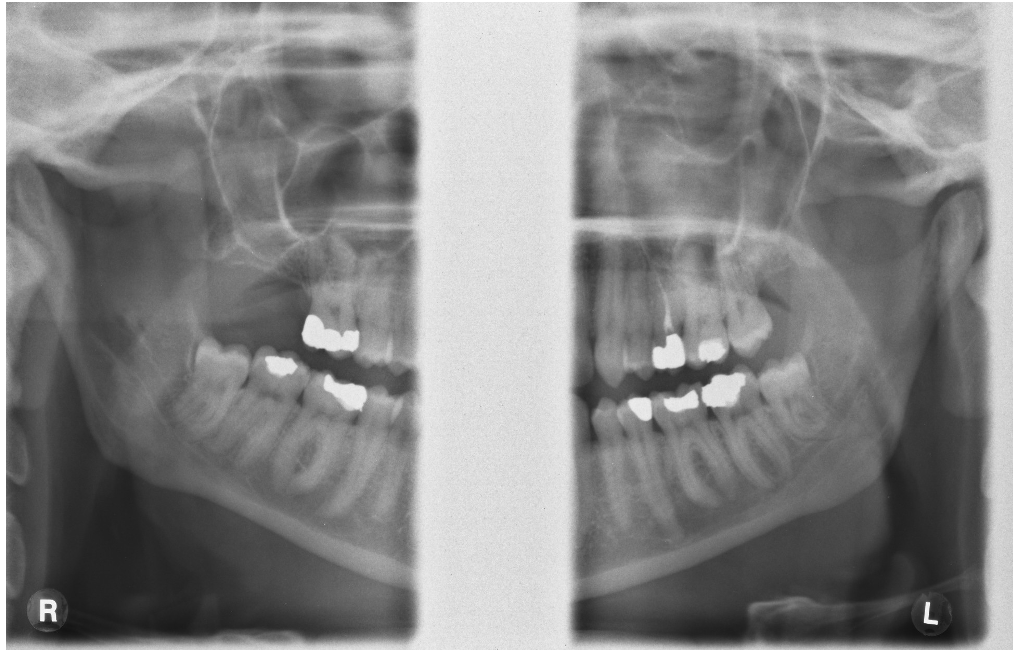

What type of impaction are these third molar?

Horizontal